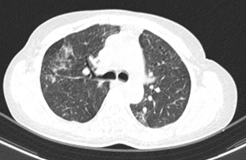

Bệnh nhân đi khám tại bệnh viện Bạch Mai được chụp cắt lớp vi tính lồng ngực phát hiện các đám tổn thương đông đặc phổi 2 bên, tổn thương đặc xương không đều các đốt sống D5, D8, D11 và xương sườn IV bên phải.

Hình 1: Hình ảnh tổn thương phổi trước điều trị: các đám tổn thương đông đặc, ranh giới không rõ, lan tỏa nhu mô phổi 2 bên.